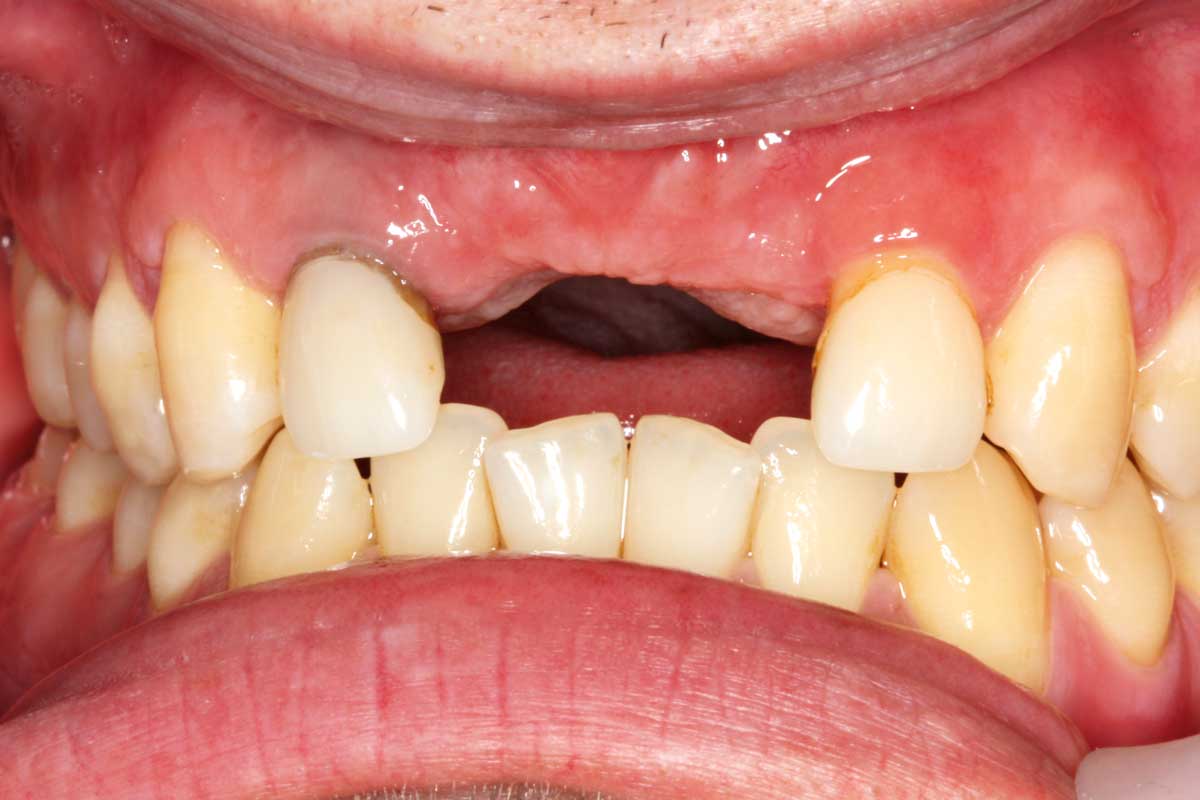

12/26 - Clinical situation after 6 months

Ridge augmentation in the maxilla with maxgraft® bonebuilder in the aesthetic zone - Dr. M. Kristensen